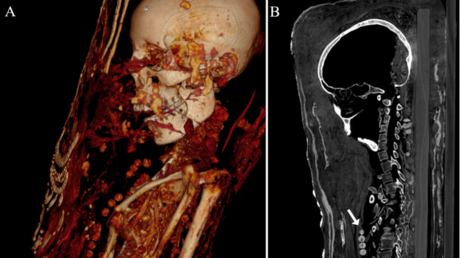

Mediante análisis de tomografía computerizada, los investigadores lograron obtener información sobre el estado de conservación de los cuerpos, la técnica de momificación artificial usada, la edad de los individuos en el momento de la muerte, así como su género, altura y salud.

En este sentido, el experto considera el hallazgo como una prueba del cambio de técnicas aplicadas en el tratamiento corporal previo a la momificación, pues la práctica común en Egipto contemplaba la eliminación del cerebro a través de los orificios de la nariz, así como de los órganos internos.

Finalmente, los resultados del estudio también revelaron otros datos relacionados con la salud de las tres momias, como la presencia de caries, protuberancias entre las vértebras (nódulos de Schmorl) y evidencia de artritis.